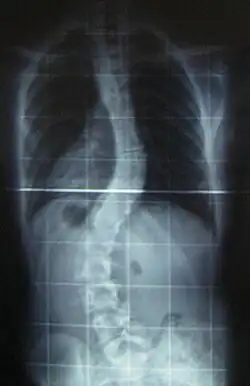

Skolioza (łac. scoliosis, z gr. σκολιός skoliós – krzywy) – skrzywienie kręgosłupa, zwane często „bocznym skrzywieniem kręgosłupa”. Wbrew tej nazwie, skolioza nie jest jedynie bocznym skrzywieniem, a trójpłaszczyznowym.

Skoliozą określa się zniekształcenie wynoszące ponad 10° w płaszczyźnie czołowej. Do określania stopnia zniekształcenia wykorzystuje się metodę Cobba.

Pierwszoplanowe znaczenie w diagnostyce skolioz ma badanie radiologiczne. Określa ono:

- stopień skrzywienia kręgosłupa, rotację, torsję oraz sklinowacenie;